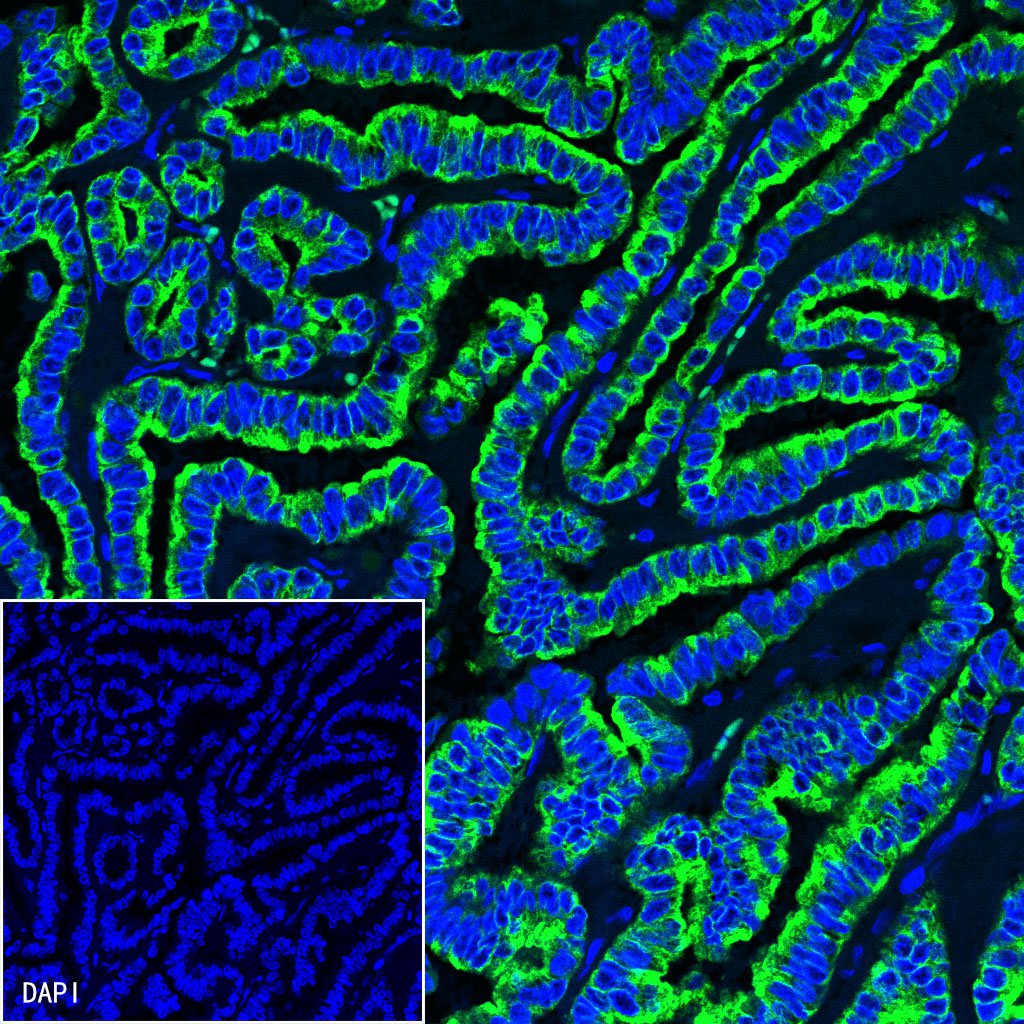

| IF |

1:500 |

Background

CK-LMW is low molecular weight cytokeratins and is expressed in monolayer or glandular epithelium of normal or tumor tissues, such as thyroid, breast, gastrointestinal or respiratory epithelium. It is expressed in adenocarcinoma and the vast majority of nonkeratinizing squamous cell carcinoma, but not in keratinizing squamous cell carcinoma. It combined with CK5/6 for diagnosis of adenocarcinoma and squamous carcinoma.